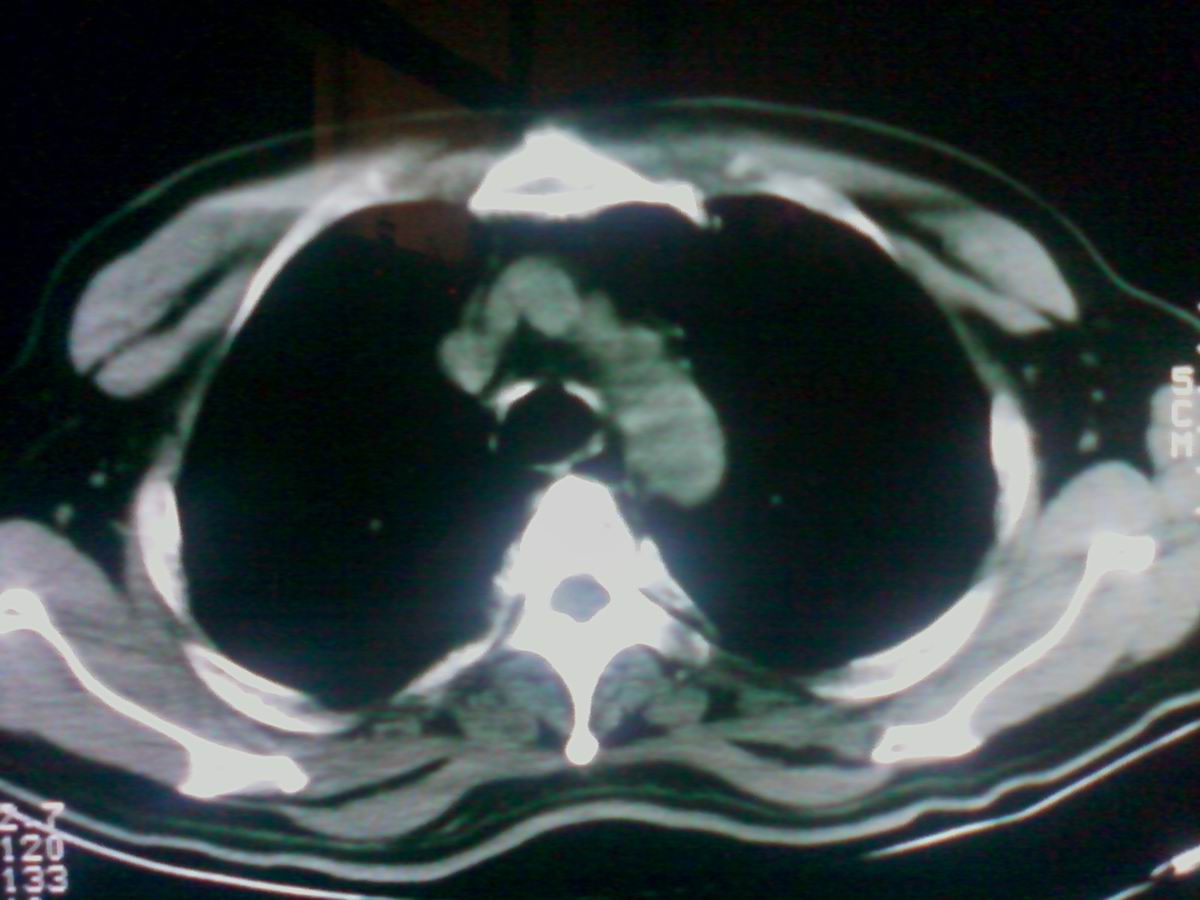

气管后部见半圆形软组织密度病灶,考虑占位,建议气管镜除外鳞癌。

气管上段的肿瘤多为良性乳头状瘤,气管下段的肿瘤多为鳞癌,气管中段的良恶性各占一半。本例位于气管下段,先按恶性处理。不过纤支镜是免不了的。

气管有占位鳞癌、腺样囊性癌、类癌、粘液表皮样癌。